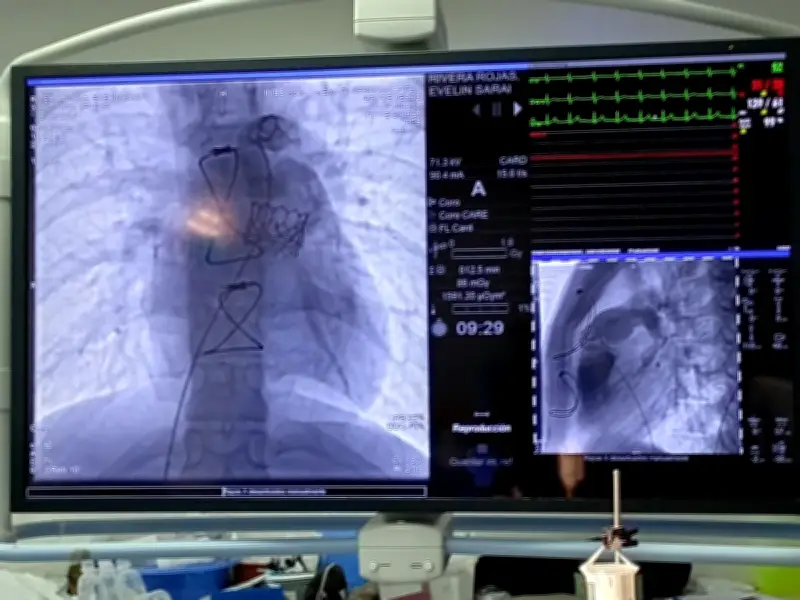

El doctor Alberto Bazzoni Ruiz, jefe del Servicio de Hemodinamia de la UMAE, explicó que el pasado 6 de marzo, Evelin, de 18 años, y Luis, de 19, ambos originarios de Durango, fueron los primeros pacientes en someterse a esta intervención. El procedimiento consiste en una punción en la vena femoral (ingle) como vía de acceso hasta el corazón, permitiendo implantar la prótesis de la válvula sin necesidad de abrir el tórax.

En marzo de este año, el doctor Teodoro de Jesús Alvarenga, cardiólogo intervencionista especializado en cardiopatía congénita, junto con un equipo multidisciplinario encabezado por el doctor Bazzoni Ruiz, realizaron la colocación de la válvula pulmonar transcatéter en ambos pacientes. El procedimiento se completó en menos de una hora en cada caso.